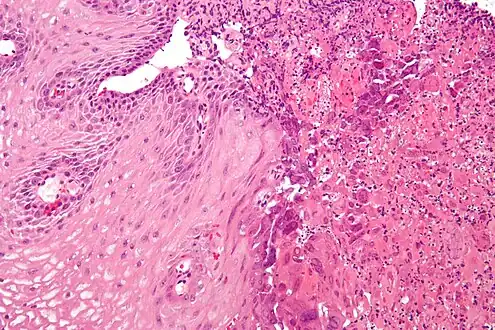

Micrograph of an esophageal biopsy showing herpes eosphagitis, with the characteristic nuclear changes (nuclear moulding, chromatin clumping at the nuclear membrane (margination) and multinucleation). H&E stain.

Micrograph of an esophageal biopsy showing herpes eosphagitis, with the characteristic nuclear changes (nuclear moulding, chromatin clumping at the nuclear membrane (margination) and multinucleation). H&E stain.

Upper Endoscopy often reveals ulcers throughout the esophagus with intervening normal-appearing mucosa. In severe cases the ulcers can coalesce and on rare occasions have a black appearance known as black esophagus.[8] While the diagnosis of herpes esophagitis can be inferred clinically it can only be accurately diagnosed through endoscopically obtained biopsies with microscopic evaluation by a pathologist finding the appropriate inclusion bodies and diagnostic immunochemical staining.[9] False negative findings may occur if biopsies are taken from the ulcer rather than from the margin of the ulcer as the inclusion particles are to be found in viable epithelial cells. Viral tissue culture represents the most accurate means of diagnosing the precise cause.